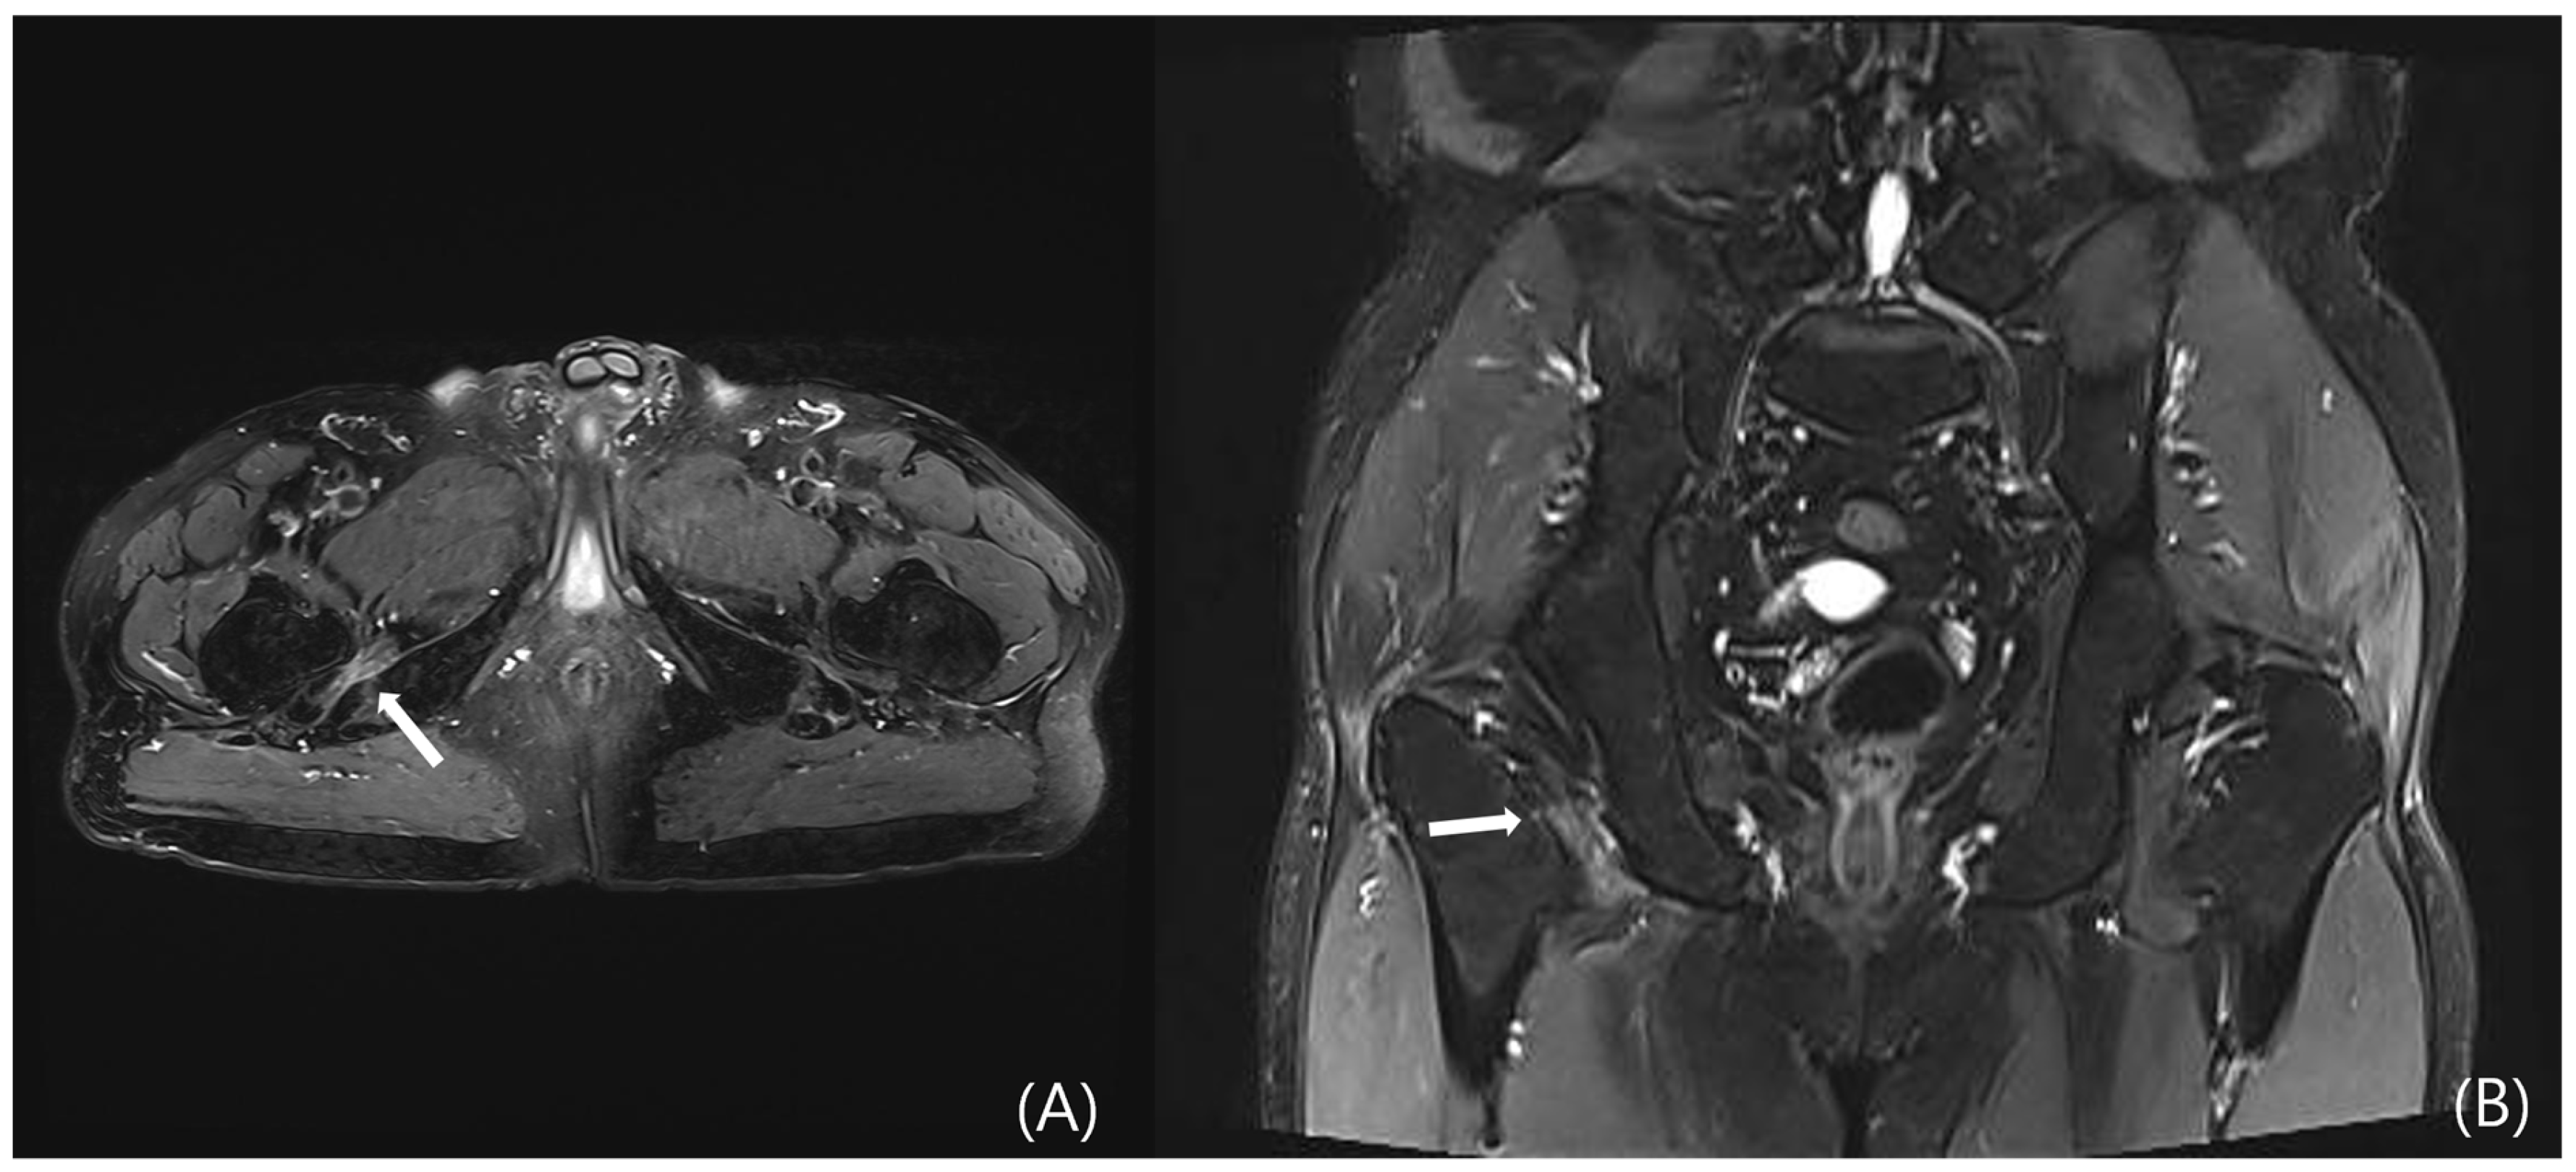

However, DGS may also result from intrinsic muscular or tendinous pathologies within the deep gluteal space. Tendon and muscle abnormalities can be evaluated by identifying peritendinous fat plane loss on T1-weighted images and increased intratendinous signal intensity and peritendinous edema on T2-weighted sequences. Tendon thickening and partial tearing may also be observed (Figure 5) [19]. Representative examples include quadratus femoris abnormalities due to ischiofemoral impingement (Figure 6) and proximal hamstring tendinopathy. Nevertheless, due to the anatomical depth and overlapping with adjacent structures, lesions involving the deep external rotators—including the piriformis, gemelli, obturator internus/externus, and quadratus femoris—are often difficult to visualize on MRI, posing diagnostic limitations.

Figure 5. Contrast-enhanced pelvic MRI of a patient who presented with left buttock pain and fever that began two days prior to admission. At the time of presentation, no erythema or warmth was noted over the buttock area, but tenderness was observed. (A) Axial and (B) coronal T2-weighted images reveal diffuse enlargement and signal intensity changes with contrast enhancement in the left piriformis, gluteus minimus, and obturator internus muscles (white arrows).